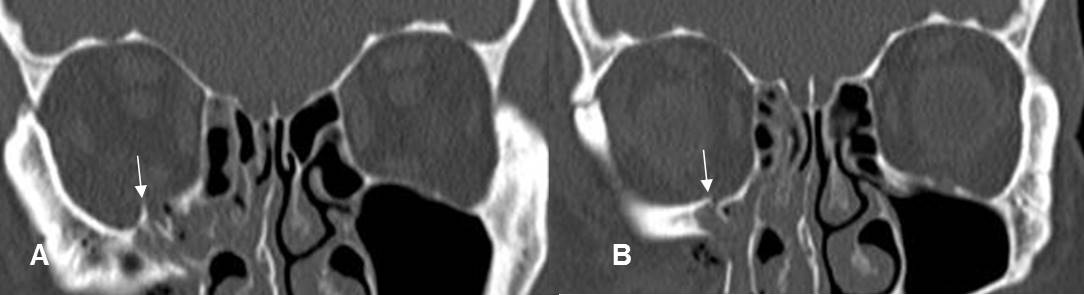

Fig 215 A. Fractura de órbita, sin atrapamiento muscular.

A y B: TAC reconstrucción coronal. Fracturas no deprimidas en el piso de la órbita y sin signos de atrapamiento muscular.